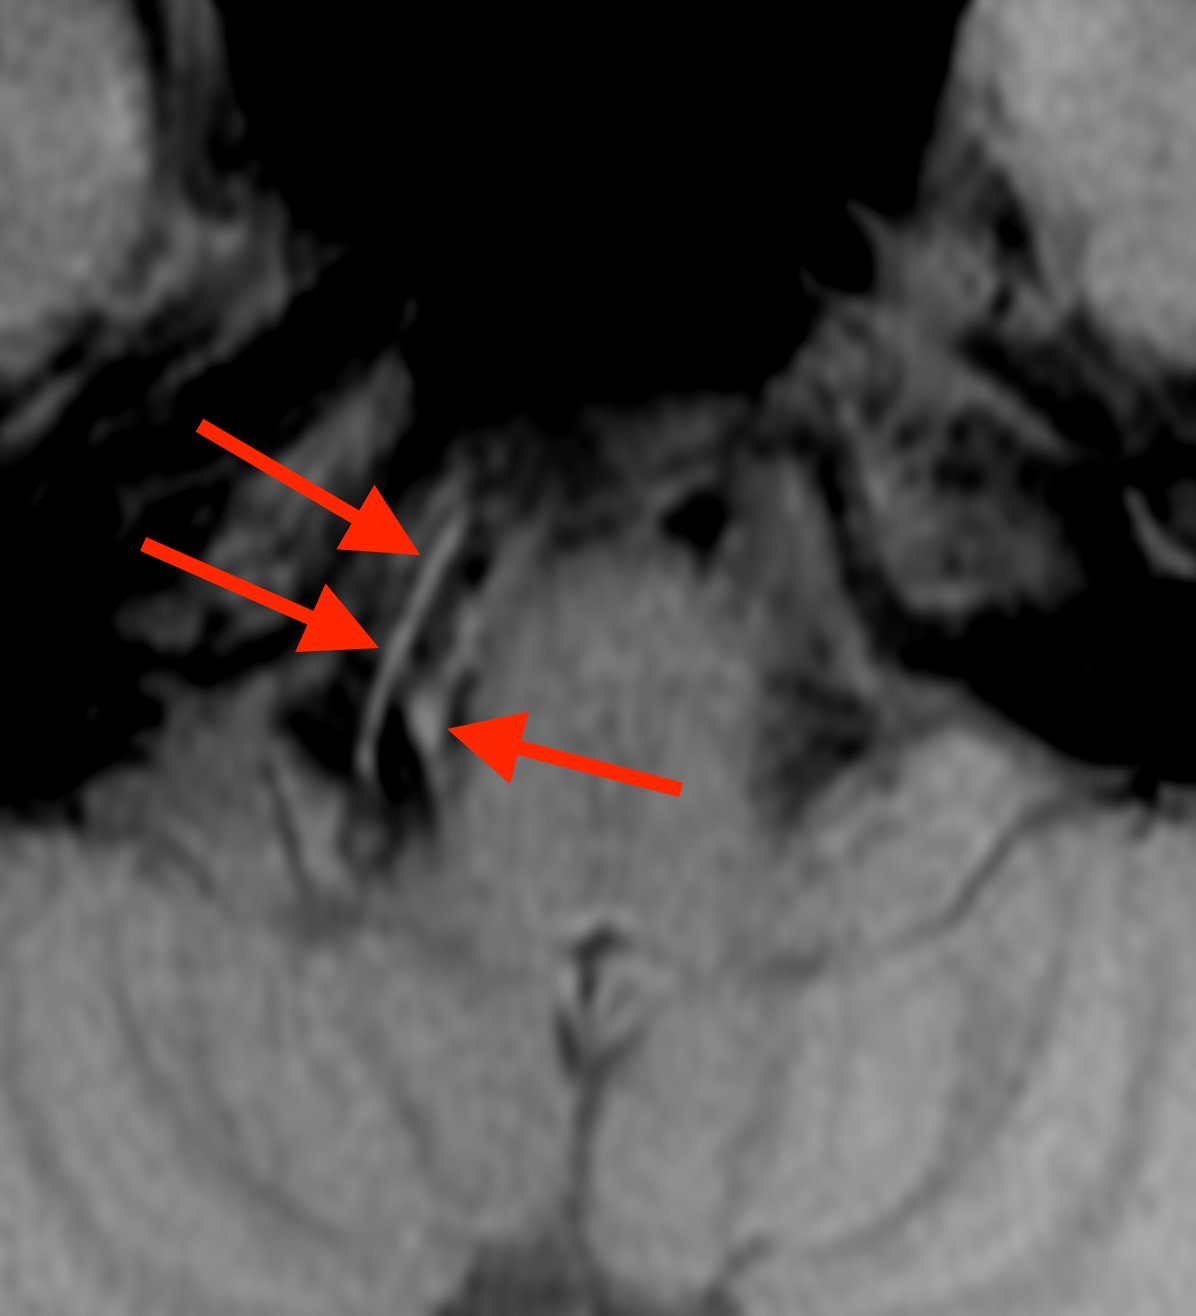

しかし、椎骨動脈解離の場合には、T1BB法(T1 black blood method)という特殊な撮像法を行うと、

このように血管壁にできた血栓(血液の固まり)が白く写ります。

この方の場合、T1BB法で見ても血栓を示す白い部分はありません。